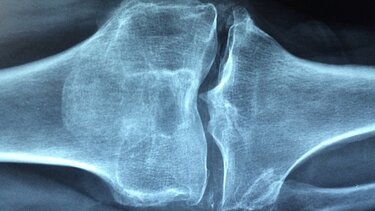

Η οστεοπόρωση είναι μια ασθένεια, που λεπταίνει τόσο πολύ τα οστά, που ακόμη και μια μικρή πτώση ή χτύπημα στην πόρτα του αυτοκινήτου ή σε ένα έπιπλο μπορεί να προκαλέσει κάταγμα. Ένα σπάσιμο μπορεί να συμβεί σε οποιοδήποτε σημείο του σκελετού σας, αλλά τα κατάγματα του καρπού, του ισχίου και της σπονδυλικής στήλης είναι από τα πιο κοινά. Σήμερα, θα δούμε τι πρέπει να κάνεις για να μην πάθεις οστεοπόρωση.

Το να διατηρείτε γερά τα οστά σας είναι ένας έξυπνος στόχος σε οποιαδήποτε ηλικία. Ωστόσο, τα οστά χωρίς κατάγματα γίνονται η μεγαλύτερη προτεραιότητα τις δεκαετίες μετά την ηλικία των 50 ετών, καθώς τα εξασθενημένα οστά οδηγούν σε σπασίματα μία στις δύο γυναίκες και έναν στους πέντε άνδρες.

Μετά την ηλικία των 50 ετών, η απώλεια οστικής μάζας ξεπερνά τον σχηματισμό νέας και η οστική απώλεια επιταχύνεται.